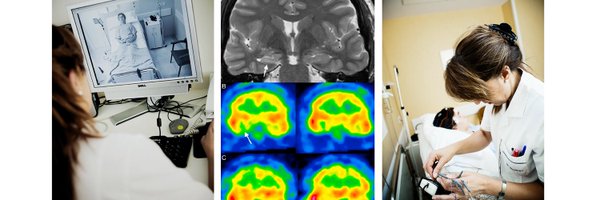

Y terminamos con una nueva charla en nuestro curso, hablando del análisis de fuentes (ESI) en la evaluación prequirurgica y cirugía de la epilepsia. Una técnica que implementamos en nuestro centro y que nos permite operar a pacientes con epilepsias de difícil localización.

Empezamos nuestro noveno curso de monitorización Video-EEG prolongada en epilepsia, con la misma ilusión que el primer día. De nuevo gracias a UCB por el apoyo y su implicación en este proyecto.